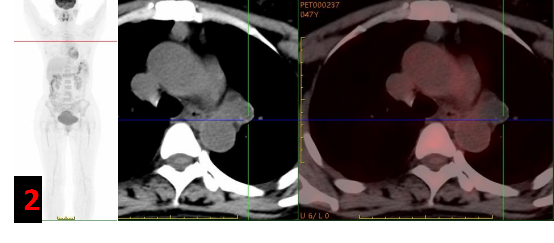

主動脈弓左旁不規(guī)則混雜密度腫塊影,邊緣見斑點狀/環(huán)形鈣化灶,FDG代謝不高(SUVmax約0.3-1),考慮良性病變(圖2)。